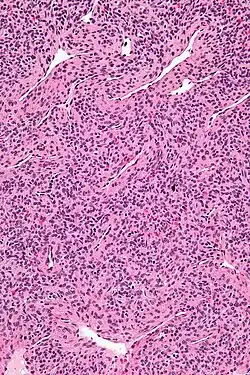

| Micrograph of a myopericytoma. H&E stain. | |